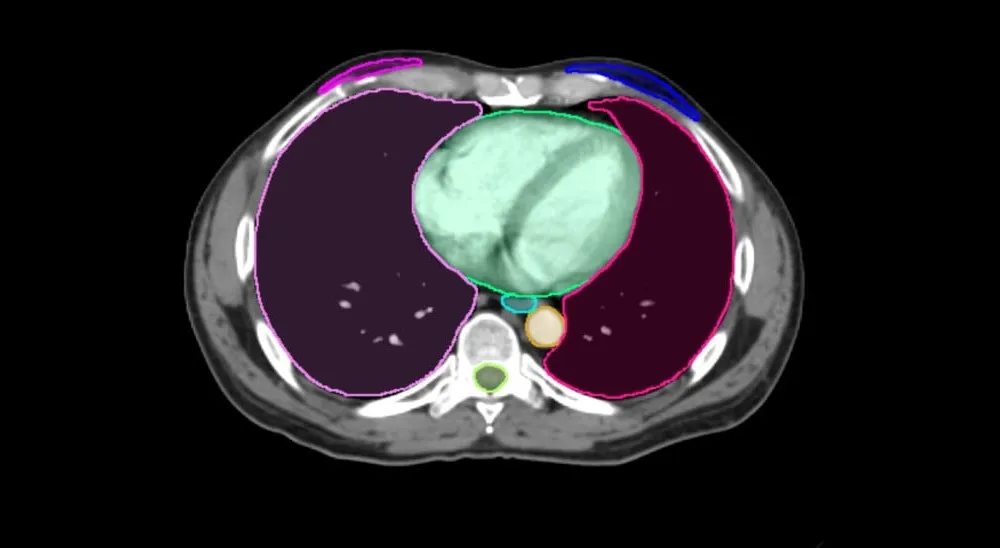

R&D Intern

May 2023 — August 2023

MIM Software, Beachwood, OH

Advised by Dr. Soroush Pahlavian

- Reviewed and presented on current literature.

- Reproduced several methodologies for adapting an open source 2D image segmentation model in order to segment 3D medical scans using publicly available code and data.

- Fine-tuned those models using a proprietary CT scan dataset.

- Summarized findings in a technical report and presented the results to MIM's R&D Team and Chief Science Officer.